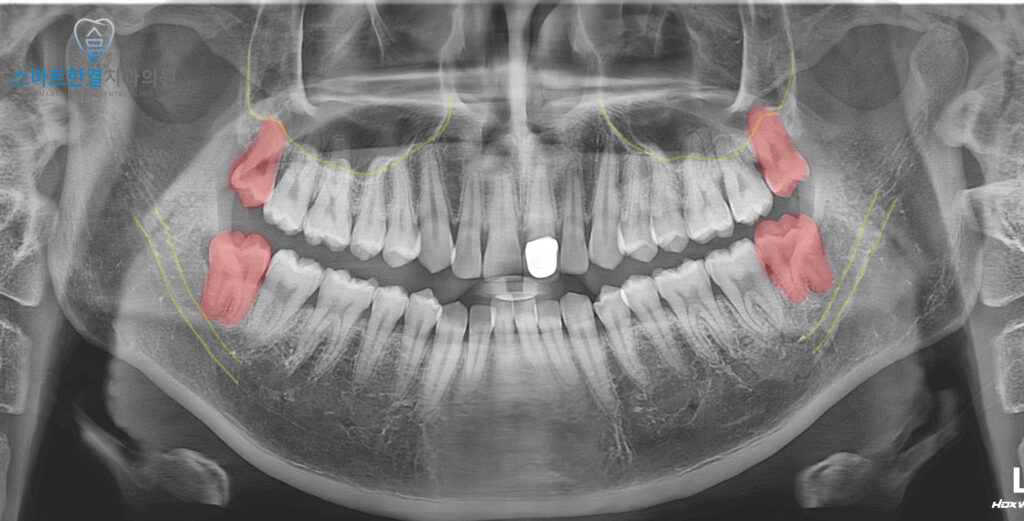

파노라마 엑스레이 사진을 통해

확인해 보니,

네 개의 사랑니 모두 비교적

정상적인 형태로 자라고 있었지만,

아래쪽 사랑니는 다른 치아와 달리

약간 턱뼈 쪽으로 기울어진 상태였어요.

환자분께서는 말씀드린

내용을 이해하시고 먼저 왼쪽부터

발치를 진행했는데요.

사진과 같이 주변 조직의 손상 없이

깨끗하게 발치 한 모습을 볼 수 있었어요.